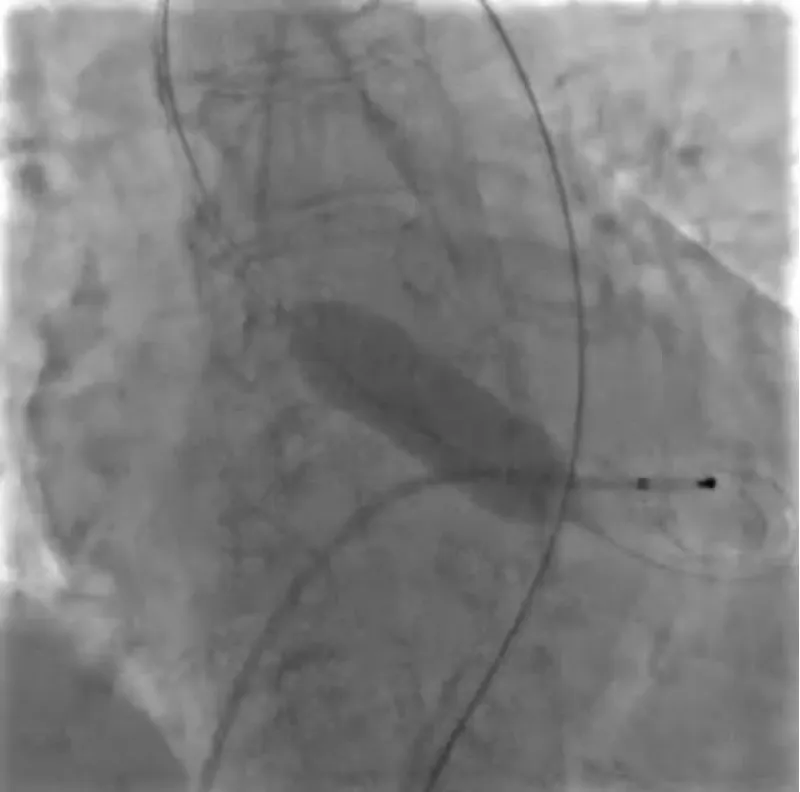

With the support of deep sedation, an angio-guided right femoral access was obtained, and a 12F introducer was advanced. We crossed the aortic valve with an Amplatzer left 1 catheter with a 0.035” wire and exchanged the wire with an extra-stiff Safari. We performed aortic Valvuloplasty with a Nucleus balloon 18 x 40 mm. (Figure 7) Then, we exchanged the wire and advanced an IMPELLA CP device, starting a protected PCI on LM. (Figure 8) An EBU 4.0 catheter was advanced, the stenosis was crossed on the Left Main (LM) and mid-Left Anterior Descending artery (LAD) using a BMW guide wire, and with the aid of a microcatheter a 0.014” Rotawire was positioned, followed by rotational atherectomy using a 1.5 mm burr on LM and mid LAD, (Figure 9) and a 2.0 mm burr on LM alone (Figure 10). This was followed by predilation with a 2.5 x 20 mm SC balloon and the implantation of a 2.5 x 32 mm Synergy drug-eluting stent (Figure 11). Then, the Left Main was predilated with a 3.5 x 12 mm NC balloon, and a 4.0 x 15 mm Xience Sierra drug-eluting stent was implanted and post-dilated with a 4.5 x 8 mm SC balloon (Figure 12). Immediate angiographic control confirmed a successful result. Then we removed the IMPELLA CP device and advanced a 14F e-sheath Edwards on the right femoral artery, crossed the aortic valve with a Safari extra-stiff wire, and performed a Sapien 3 23 mm valve implantation with a good angiographic result (Figure 13). Post-procedural echocardiographic and angiographic assessment confirmed the valve was correctly positioned, with no significant gradient and a minimal residual leak. The procedure was uneventful, and the patient was discharged on the fourth day with triple therapy: Aspirin 100 mg once daily, Clopidogrel 75 mg once daily, and Apixaban 2.5 mg twice daily. At the quarterly follow-up, the patient reported hospitalization for anemia, requiring a transfusion of 3 units of packed red blood cells. Endoscopic exams were negative, and hypochromic, normocytic anemia persisted. Given the patient’s CHA2D2-VASc score of 5, HAS-BLED score of 4, and recent dual Drug-Eluting Stent (DES) implantation, she was admitted for left atrial appendage percutaneous closure. Before this procedure, a repeat coronary angiography showed good results in the previously implanted stents (Figure 14). Subsequently, through a right femoral percutaneous approach using a 12F introducer, a 22 mm Amulet device was positioned for left atrial appendage closure (Figure 15). The procedure was completed without complications. At the 4-year follow-up, the patient presented in good hemodynamic status, with an echocardiographic ejection fraction of 55%. She continued on clopidogrel 75 mg once daily therapy.

Figure 5: CT angiographic visualization of the vascular access route, displaying the right common femoral artery with a mean diameter of 6.1 mm^2 and the external iliac artery at 8.4 mm^2. Moderate tortuosity without significant calcification is noted, aiding in the strategic planning of vascular access for the percutaneous intervention.